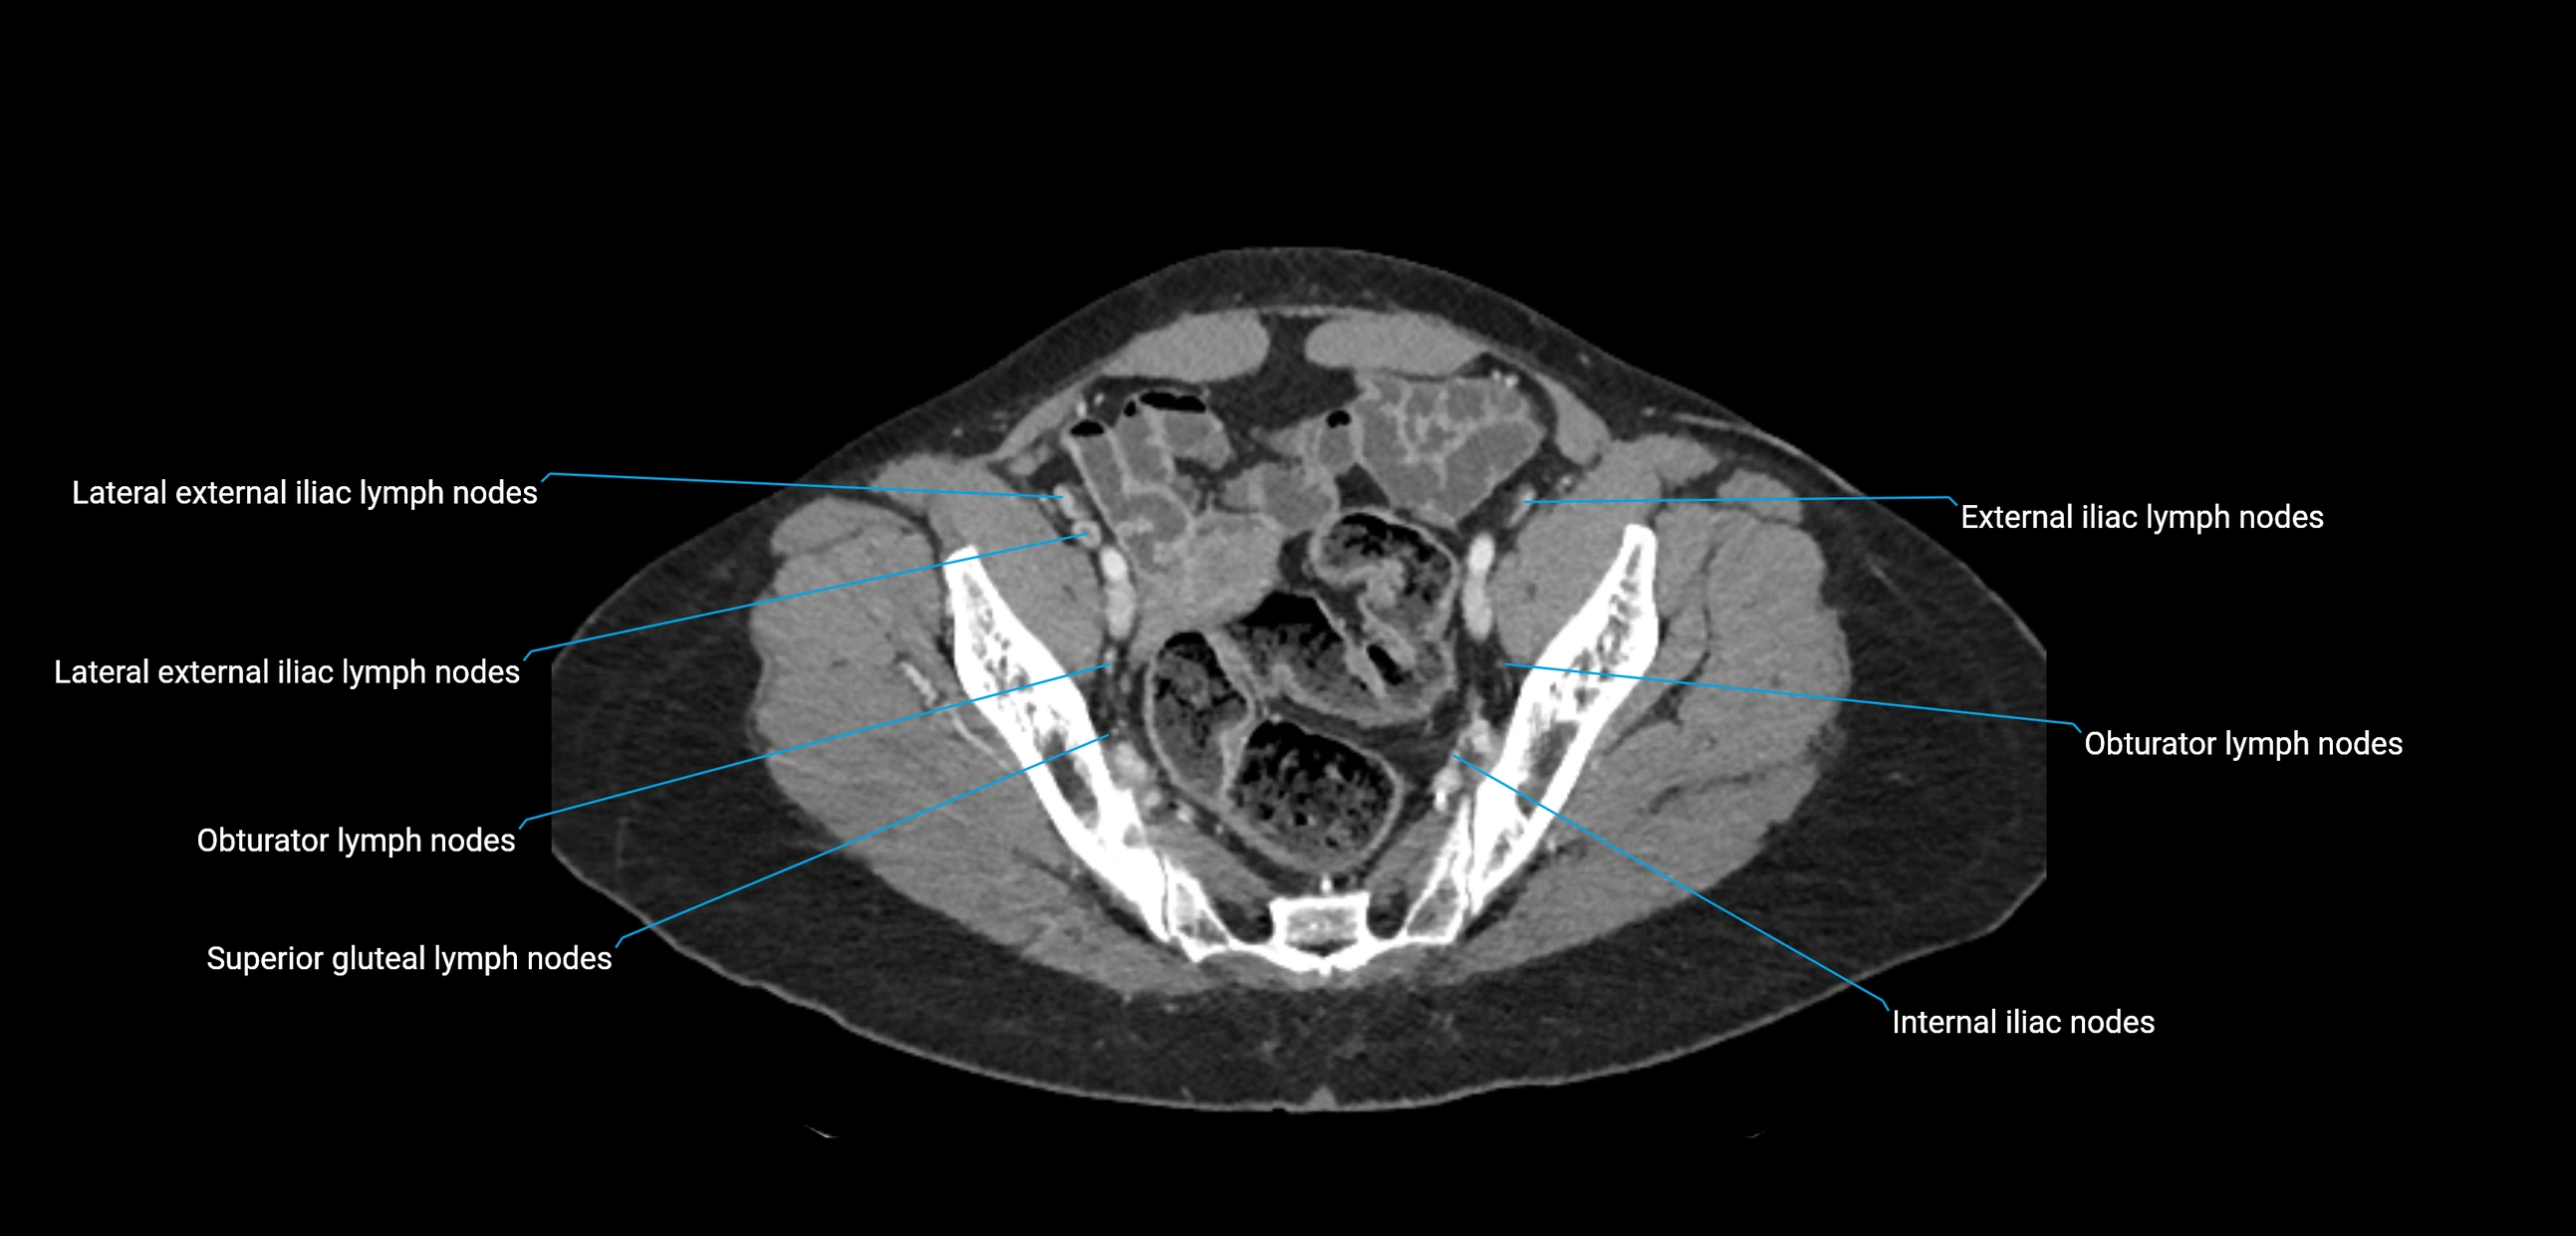

CT Appearance

CT Pre-Contrast:

• Nodes appear as soft-tissue density nodules adjacent to the aorta and IVC

• Calcification may be seen in chronic infections (e.g., tuberculosis)

CT Post-Contrast:

• Normal nodes enhance homogeneously

• Malignant nodes may show heterogeneous enhancement, central necrosis, or conglomerate formation

• Size >1 cm short axis is suspicious, though morphology and distribution are equally important